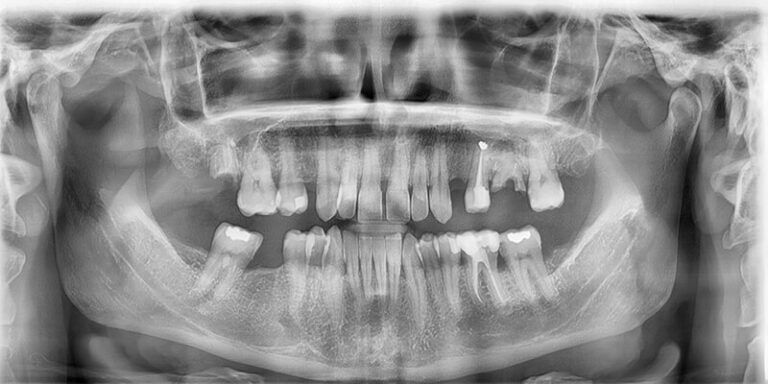

Paciente de 46 años acude a la consulta interesado en reponer las piezas ausentes.

En la primera visita se le diagnostica y presupuesta la exodoncia de restos radiculares en 17 y 26 y la realización de curetajes en ambas arcadas, así como la obturación de 2 caries proximales en 27 y 37.

También se le explica la necesidad de una fase ortodóncica previa a la reposición protésica de las piezas ausentes 14,24,26 y 46, cuyo objetivo es la alineación del sector anterior superior y la intrusión del mismo, especialmente del 23 y el cierre de los diastemas presentes, centrando la línea media y mejorando los espacios para la colocación de los respectivos implantes y sus correspondientes coronas.